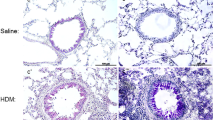

Having shown that IL-15Cx has interesting properties and plays a role in modulation of NK cells, CD8+ lymphocytes and T regulatory lymphocytes, we aimed to evaluate effect of IL-15Cx in airway inflammation induced by house dust mite (HDM). Asthma results in chronic inflammation of the lower airways, bronchoconstriction and bronchial hypersecretion, associated with bronchial remodeling (smooth muscle hypertrophy, epithelial cell hyperplasia, basement membrane thickening). We decided to analyze these different pillars of pathophysiology with a murine model of allergic asthma to HDM (Fig. 4a) characterized by a mixed inflammation Th2 and Th17 [15]. We verified the levels of endogenous human and mouse IL-15 after injection of the complex in wild type mice and in asthma challenged mice. As expected, endogenous mouse IL-15 levels were not modified after IL-15Cx injection, but human IL-15 levels were increased (data not shown). An essential component for studying asthma is bronchial hyperreactivity. This can be evaluated by an invasive method that uses forced oscillometry, Flexivent®. We performed it on control group (CTL), asthmatic mice group (HDM group) and on asthmatic mice treated by IL-15Cx group (HDM IL-15Cx group) (Fig. 4b). As expected, asthmatic mice showed an increase in lung resistances in response to increasing doses of methacholine compared to control mice. However, there was no difference in pulmonary resistance between the asthmatic and asthmatic IL-15Cx treated mice. To better understand the lack of effect of the IL-15Cx on bronchial hyperreactivity, we performed histology on lung tissue to measure anatomical observation (Fig. 4c-d). In HDM mice, we observed a strong peri-bronchial and perivascular cell infiltrate, as well as hyperplasia of the epithelium with the appearance of numerous mucus cells (Fig. 4c). The evaluation of this histological score confirms a significant increase in the score between CTL and HDM groups (Fig. 4d). As for lung resistances, we did not show any reduction in the histological score between the HDM and HDM IL-15Cx groups. Mucus production is increased in asthma and contributes to increase pulmonary resistance. We evaluated mucus production on our model by calculating a score of goblet cells colored by periodic acid of Schiff (Fig. 4c). We found an increase in this score between CTL and HDM groups (Fig. 4d). We also observed a decrease in the score between the HDM group and the HDM IL-15Cx group. This decrease, however, seems insufficient to improve the respiratory function of our asthmatic murine model. To better assess lung inflammation in our model, we performed broncho-alveolar lavages. We found an increase in eosinophil count in our asthma model but IL-15Cx injection did not decrease eosinophilia (Fig. 4e). Then the inflammatory action of the IL-15 complex, was analyzed in lungs, mediastinal lymph nodes and spleen in HDM and HDM IL-15Cx mice. We first evaluated NK cells (NKP46+, DX5+, CD3−) (Fig. 5). In lungs and in mediastinal lymph nodes we found no significant difference after the injection of the IL-15Cx (Fig. 5a-b). However, we found an increase in NK cells in the spleen between HDM and HDM IL-15Cx groups. In the allergic asthmatic murine model, IL-15 complex injected intraperitoneally has an effect on NK cells in spleen but not in local sites of inflammation. Then, we explored adaptative immunity to investigate whether the complex modulates inflammation (Fig. 6). Regarding memory CD8+ lymphocytes (CD8+, CD44+, CD122+), there was no statistical difference in the lungs and in the spleen (Fig. 6a-b) between groups. The percentage of CD8+ CXCR3+ lymphocytes was not increased in the lungs after the injection of the complex (Fig. 6c) but it tended to increase in the spleen (8,66% versus 12,54% respectively, p = 0,07) (Fig. 6d). Moreover, the percentage of Th1 lymphocytes (CD4+, CD25+, CXCR3+) was not modified in the lungs (Fig. 6e) nor in the spleen (Fig. 6f). T regulatory lymphocytes (CD4+, CD25+, FOXP3+) were not modified in the spleen (Fig. 6h) but tended to increase in the lungs (6,24% versus 3,67% respectively, p = 0,07) (Fig. 6g). In conclusion, we did not find any impact on the adaptative immunity with the IL-15 complex in our model of allergic asthma.

Asthma features are not improved by IL-15 complex. a Murine model of acute allergic asthma. Sensitization of Balb/c mice by four percutaneous applications of 500 μg of total mite extracts (HDM). For challenges, 250 μg of HDM were inoculated intranasally (IN). Four injections of the IL-15 complex and its soluble alpha receptor (IL-15 Cx) were administered intraperitoneally (IP) once daily between the two challenges. Analysis were made the day after the second challenge. b Airway resistance (RI; cmH2O/mL) in anesthetized CTL, asthmatic group (HDM) and asthmatic mice treated by IL-15Cx (HDM IL-15 Cx), in response to various concentrations (0, 5, 10, 15, 20 mg/mL) of methacholine were measured with Finepoint RC system. c Lungs were perfused with 4% paraformaldehyde solution and stained with hematoxylin and eosin (H&E) or periodic Schiff acid (PAS). Bronchial histology was performed for CTL, HDM and HDM IL-15 Cx group. Blue arrows: inflammatory peri-bronchovascular infiltrate. Black arrows: goblet cells colored with PAS. Scale = 100 μm (d) Histological sections were scored on 12 points; 4 points are devoted to morphological alteration and 8 points to inflammation (n = 3 to 7 mice per group); The PAS score was calculated on 5 bronchial sections per group, as the number of positive PAS cells (black arrows) reported to the total number of epithelial cells of this bronchus. e Eosinophils (CD3-, CCR3+) were measured in bronchoalveolar lavage fluid by flow cytometry. The cells were collected by washing the lung with 1 ml of PBS after tracheostomy.* p < 0.05, ** p < 0.01 using Mann-Whitney test. ns = not significant